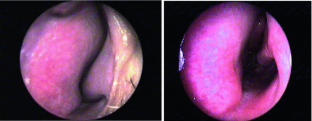

Fig. 1

Fig. 2